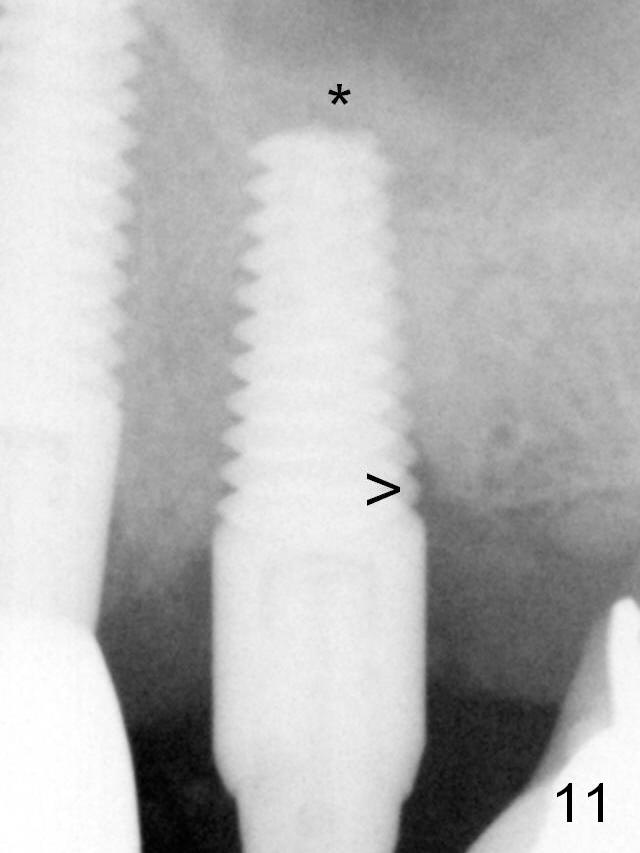

The distal threads appear not covered by the bone 2.5 months postop (Fig.11 >).